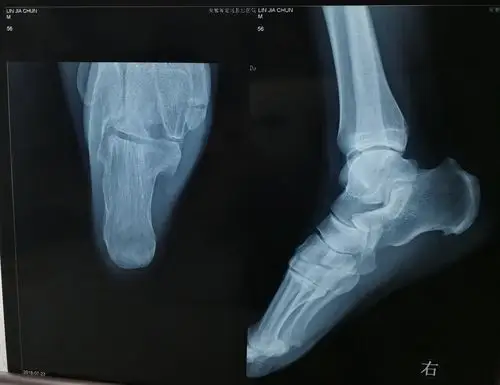

【足踝篇】 000 右侧跟骨骨折并跟距关节脱位(病例展示)

患儿,男,11岁,跟骨骨骺炎,跟骨侧位片可见跟骨骨